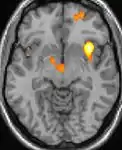

La tomographie par émission de positons (TEP) montre les zones du cerveau étant activées durant la douleur

Les images par tomographie à émission de positron indiquent les régions du cerveau qui sont activées lors de la douleur, par rapport aux périodes sans douleur. Elles montrent les régions du cerveau qui sont toujours actives durant la douleur en jaune/orange (appelé "matrice-douleur"). La zone au centre (dans les trois vues) est spécifiquement activée uniquement pendant la crise. Les photos sur la ligne du bas (effectuées par VBM) montrent les différences structurelles entre les patients souffrant d'AVF et des personnes saines : seulement une partie de l'hypothalamus est différente[50],[51].